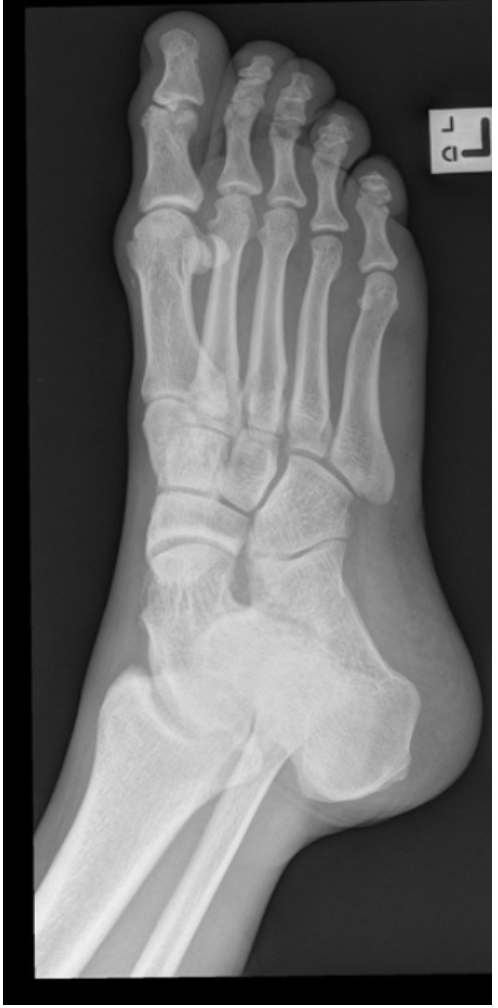

7

Q

What view is this?

A

DP